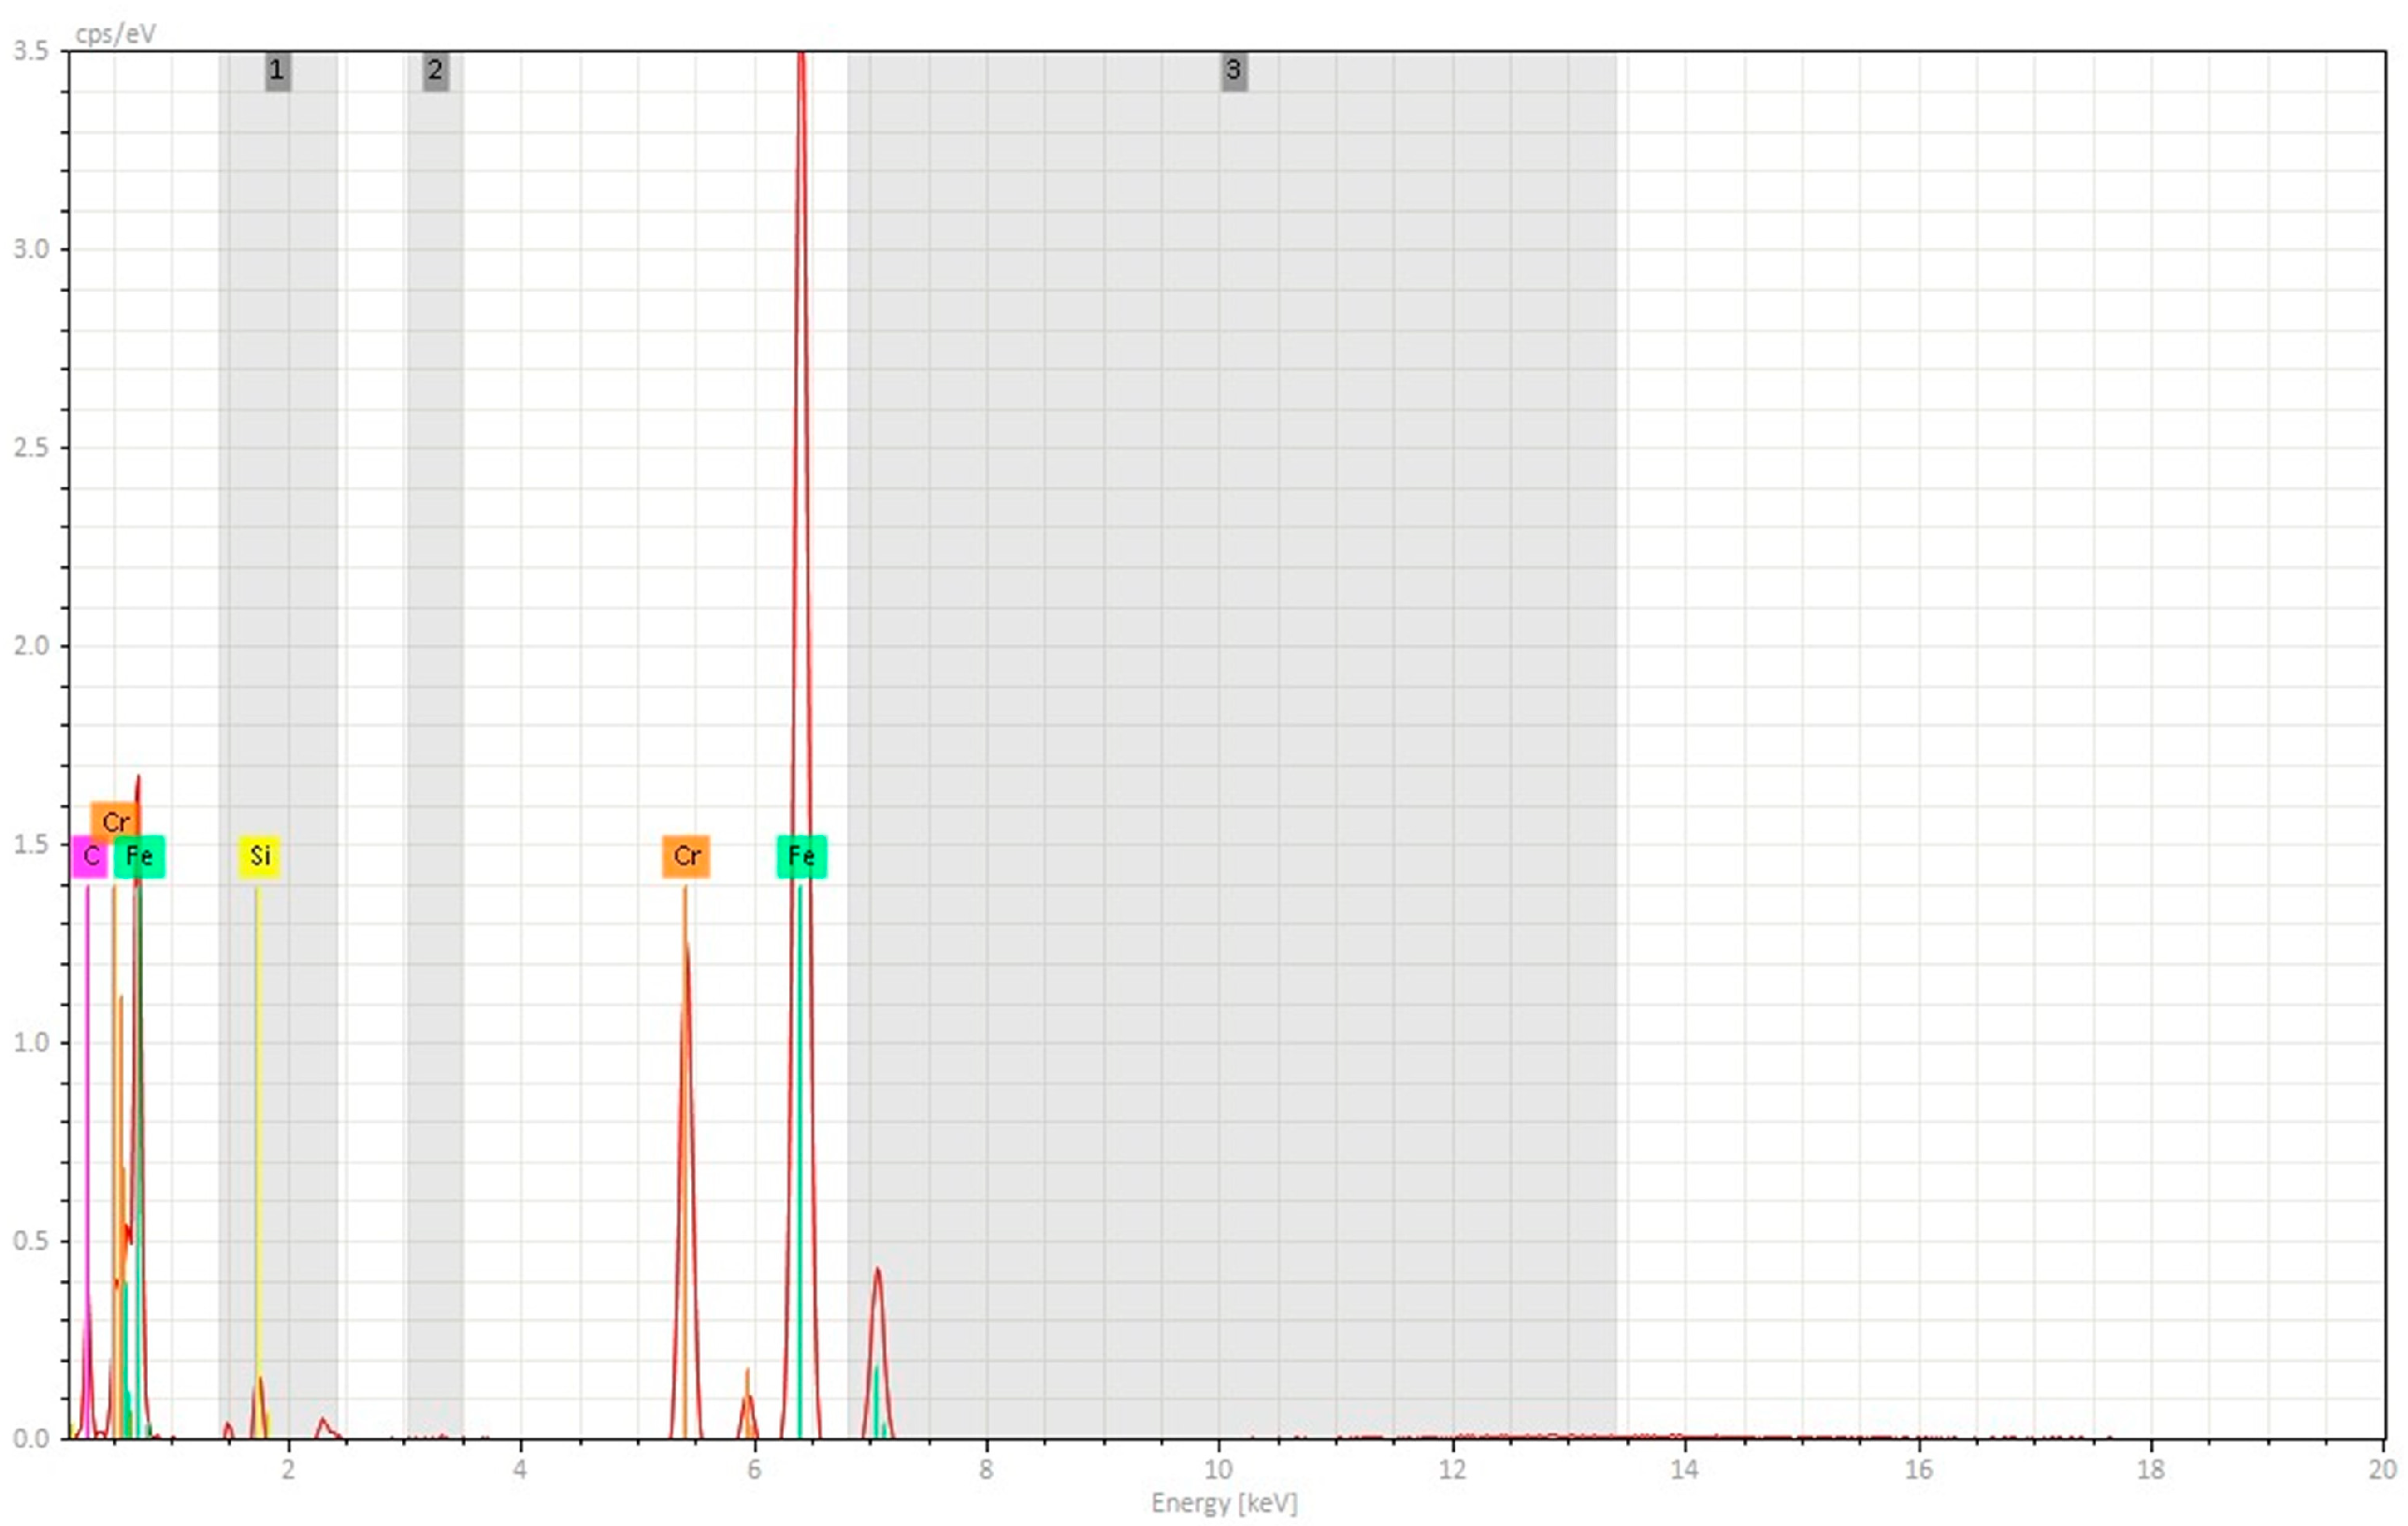

3.2. Scanning Electron Microscopy-EDS Analysis

3.2.1. Non-Sterilized Drill and Conical Tapper

3.2.2. Used and Sterilized Drill and Conical Tapper